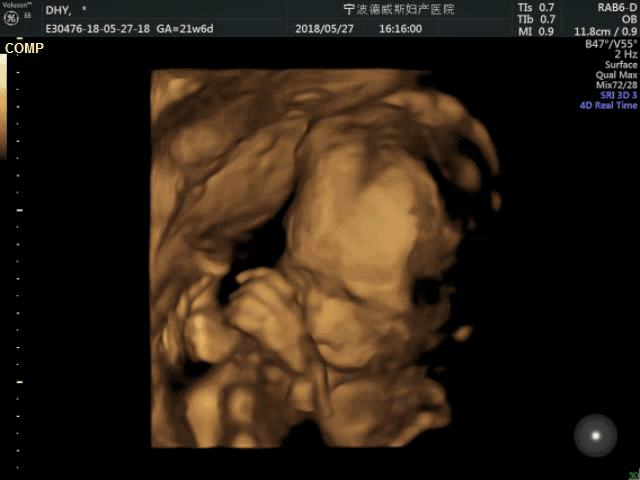

做四维彩超需要吃东西去吗,多少周合适?四维彩超是大排畸中重要的一个手段,大排畸用二维、还有三维彩超,但是四维是三维彩超的升ji版,所以它的清晰度、准确度都是比较高的,很多孕妈对四维彩超的原理还不懂,四维是通过声波检查胎儿的情况,所以对于孕妈的腹部脂肪厚度有一定要求,如果脂肪太厚,那么很容易导致医生看不清楚、需要多次检查 。

四维彩超的时间从检查的时间范围来说,四维彩超的时间是20-24周,但是孕妈要结合自己的最后一次月经时间,有没有紊乱,提前或者推迟,如果孕妈月经提前一周,那么最好的检查时间是21周,如果是月经推迟,那么可以23周再检查,这样就可以在胎儿22周的时候检查,这个时候胎儿的大小和羊水量是最合适的,检查可以更加清楚,用时也会更加快 。